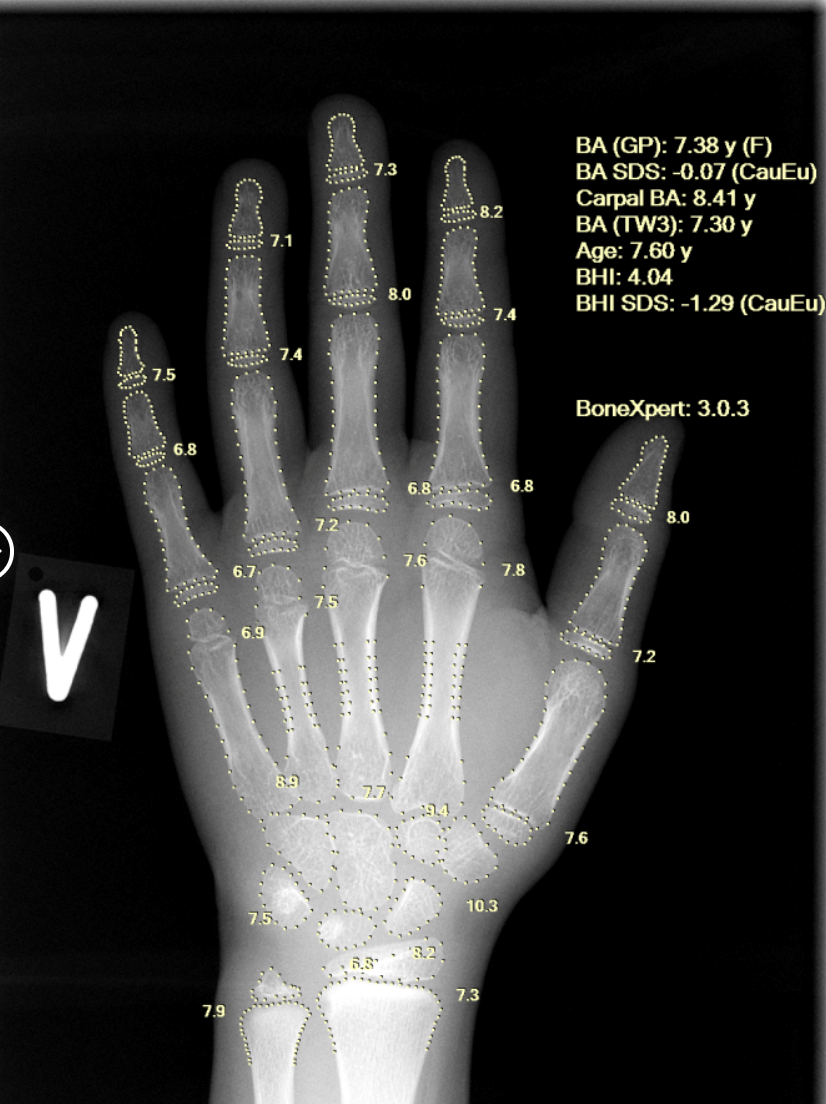

Developed by a Europe-based AI med-tech company and CE-approved, BoneXpert is considered a gold-standard solution for automated bone age assessment. The technology enables objective, accurate, and highly reproducible bone age analysis, eliminating inter- and intra-observer variability and ensuring consistent results from the same X-ray every time.

Using a single left-hand X-ray, BoneXpert provides a comprehensive, multi-method assessment, including Greulich-Pyle (GP) bone age, Tanner-Whitehouse (TW2/TW3) bone age, carpal bone age, as well as Bone Age SDS and Bone Health Index (BHI). This depth of analysis enhances diagnostic confidence and supports clinicians in early identification of constitutional growth delay and endocrine abnormalities at an early stage.